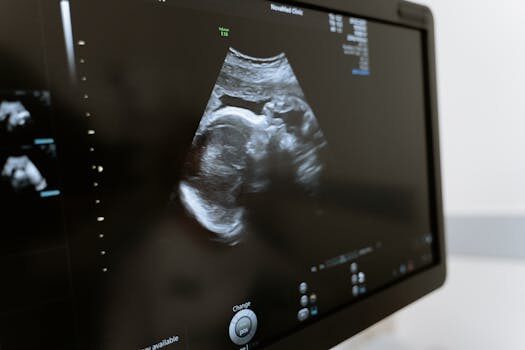

Es fundamental recordar que cada embarazo es único. Por lo tanto, no te angusties si tu barriga no se ve como las de otras mujeres. La mejor manera de asegurarte de que todo va bien es realizarte ecografías y chequeos regulares con tu médico.